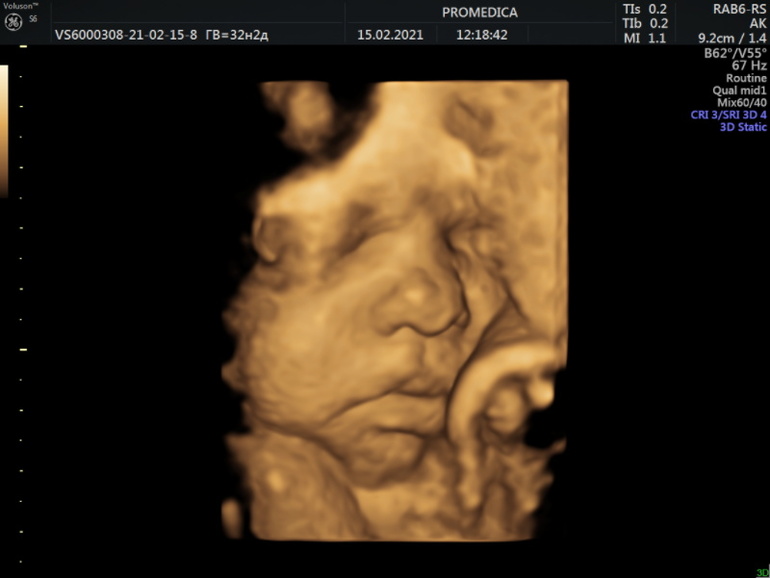

- Была на 3 скрининге, правда 2 раза. 1 раз пошла на бесплатный в наше жк - там она конечно такой чухни написала мне(прикрепление плаценты по передней стенке, хотя всю беременность было по задней). Потом я пошла второй раз на платный скрининг. Там все нормально) Мы уже весим 2050 гр)) Сделали фото и видео в 3д);